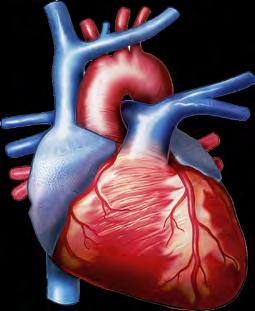

кровоносна, яка вможливлює транспортування різноманітних речовин по організму, а також бере участь

(іл. 56 ). Опорно-рухова система містить кістки й скелетні м’язи. Вона виконує захисну, опорну, рухову, метаболічну, кровотворну й терморегуляційну функції (іл. 58).